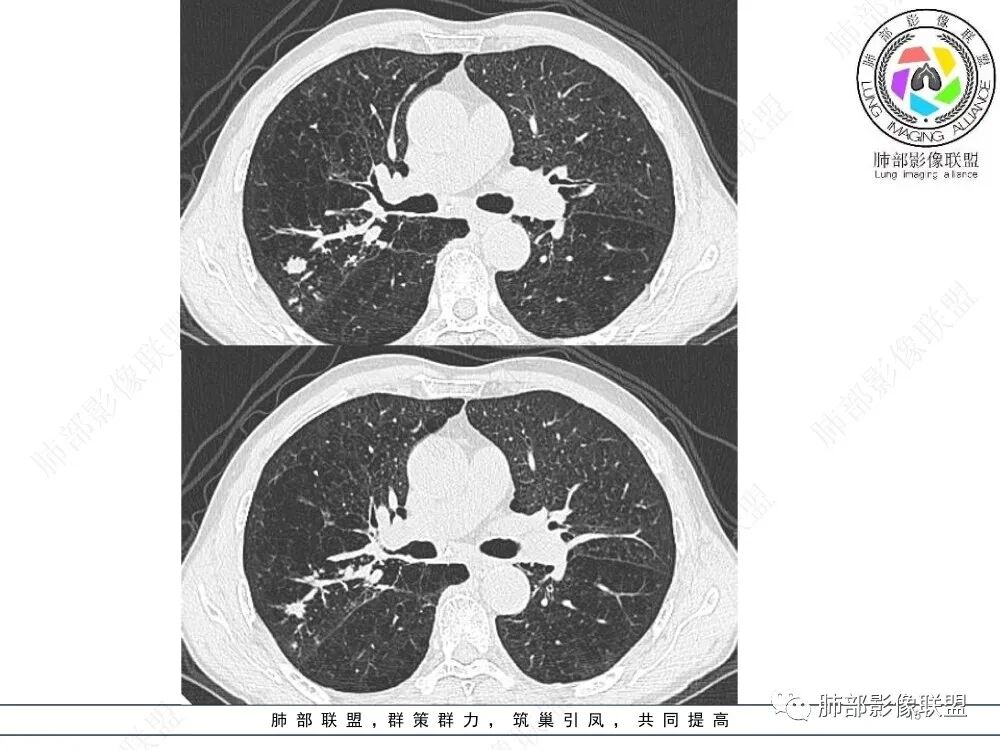

五、支气管结核

又称支气管内膜结核(EBTB),是指发生在气管、支气管粘膜和粘膜下层的结核病。成人EBTB最常见的感染途径是肺内病灶中结核分支杆菌直接植入支气管粘膜,其次肺内病灶也可通过支气管周围组织侵及支气管粘膜;结核分支杆菌也能经血行播散和淋巴引流首先侵袭支气管粘膜下层,然后累及粘膜层。儿童EBTB多因邻近纵隔淋巴结核侵蚀支气管,引起结核性支气管炎。原发性支气管结核较少见。

影像征象1:

影像征象2:

影像征象3:

上图,支气管结核。病灶多灶性、多态性。支气管中近端受累,支气管壁增厚不均匀,狭窄后扩张,伴随树芽征、钙化。